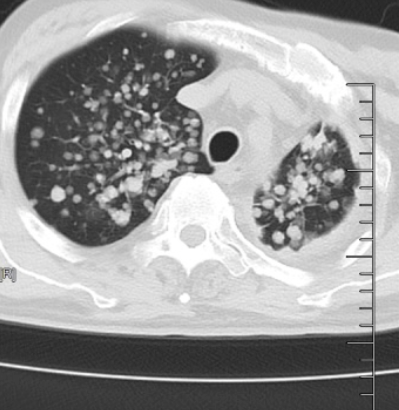

△原发性肺癌伴双肺弥漫多发转移瘤

庄兴俊主任给患者安排了胸部CT,检查结果很快传来:

🚫原发性肺癌伴双肺弥漫多发转移瘤

🚫双肺胸膜弥漫增厚

🚫纵隔淋巴结也已被肿瘤侵犯

🚫肺部成了肿瘤蔓延重灾区